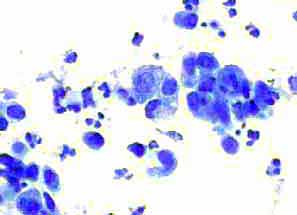

Aσθενής 45 ετών, με γνωστή παρουσία πολλαπλών κύστεων και στους δύο μαστούς εδώ και πολλά χρόνια.. Επώδυνη κύστη διαμέτρου 4 εκ. στον αριστερό μαστό. Κάτω από υπερηχογραφικό έλεγχο παρακέντηση και αφαίρεση περίπου 20 κ. εκ. κιτρινωπού υγρού.